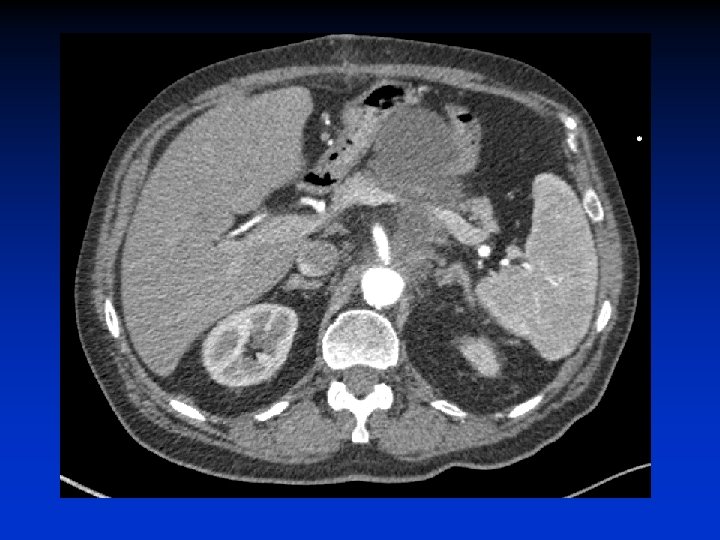

Narrow Bifurcation Department of Surgery, University of Pennsylvania Health System

§ Healthy neck § “friendly” anatomy § 55 yo § CRI: Cr 1. 8 Department of Surgery, University of Pennsylvania Health System